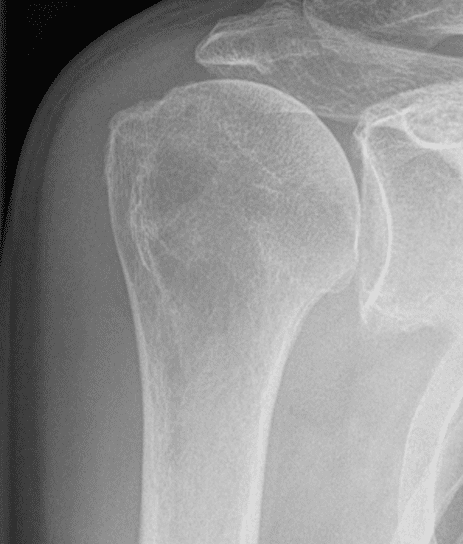

Patient Cases

One of LINK’s major objectives in joint arthroplasty is the preservation of vital bone. In the LINK Embrace Shoulder System, Humeral Short Stems as well as Stemless Cages help to save valuable bone stock for possible future treatments and revisions. For stemless primary reverse arthroplasty, the LINK Embrace Shoulder System offers Stemless Ring Cages, designed for direct connection to the required Reverse Insert. Stemless Ring Cages may also be used for anatomic reconstruction with both Humeral Heads and CTA Heads by means of specific adapters. Bone contact areas of LINK Embrace Stemless Cages and Stemless Ring Cages are equipped with a TrabecuLink surface, aiming at good primary stability as well as fast and long lasting bony integration.1